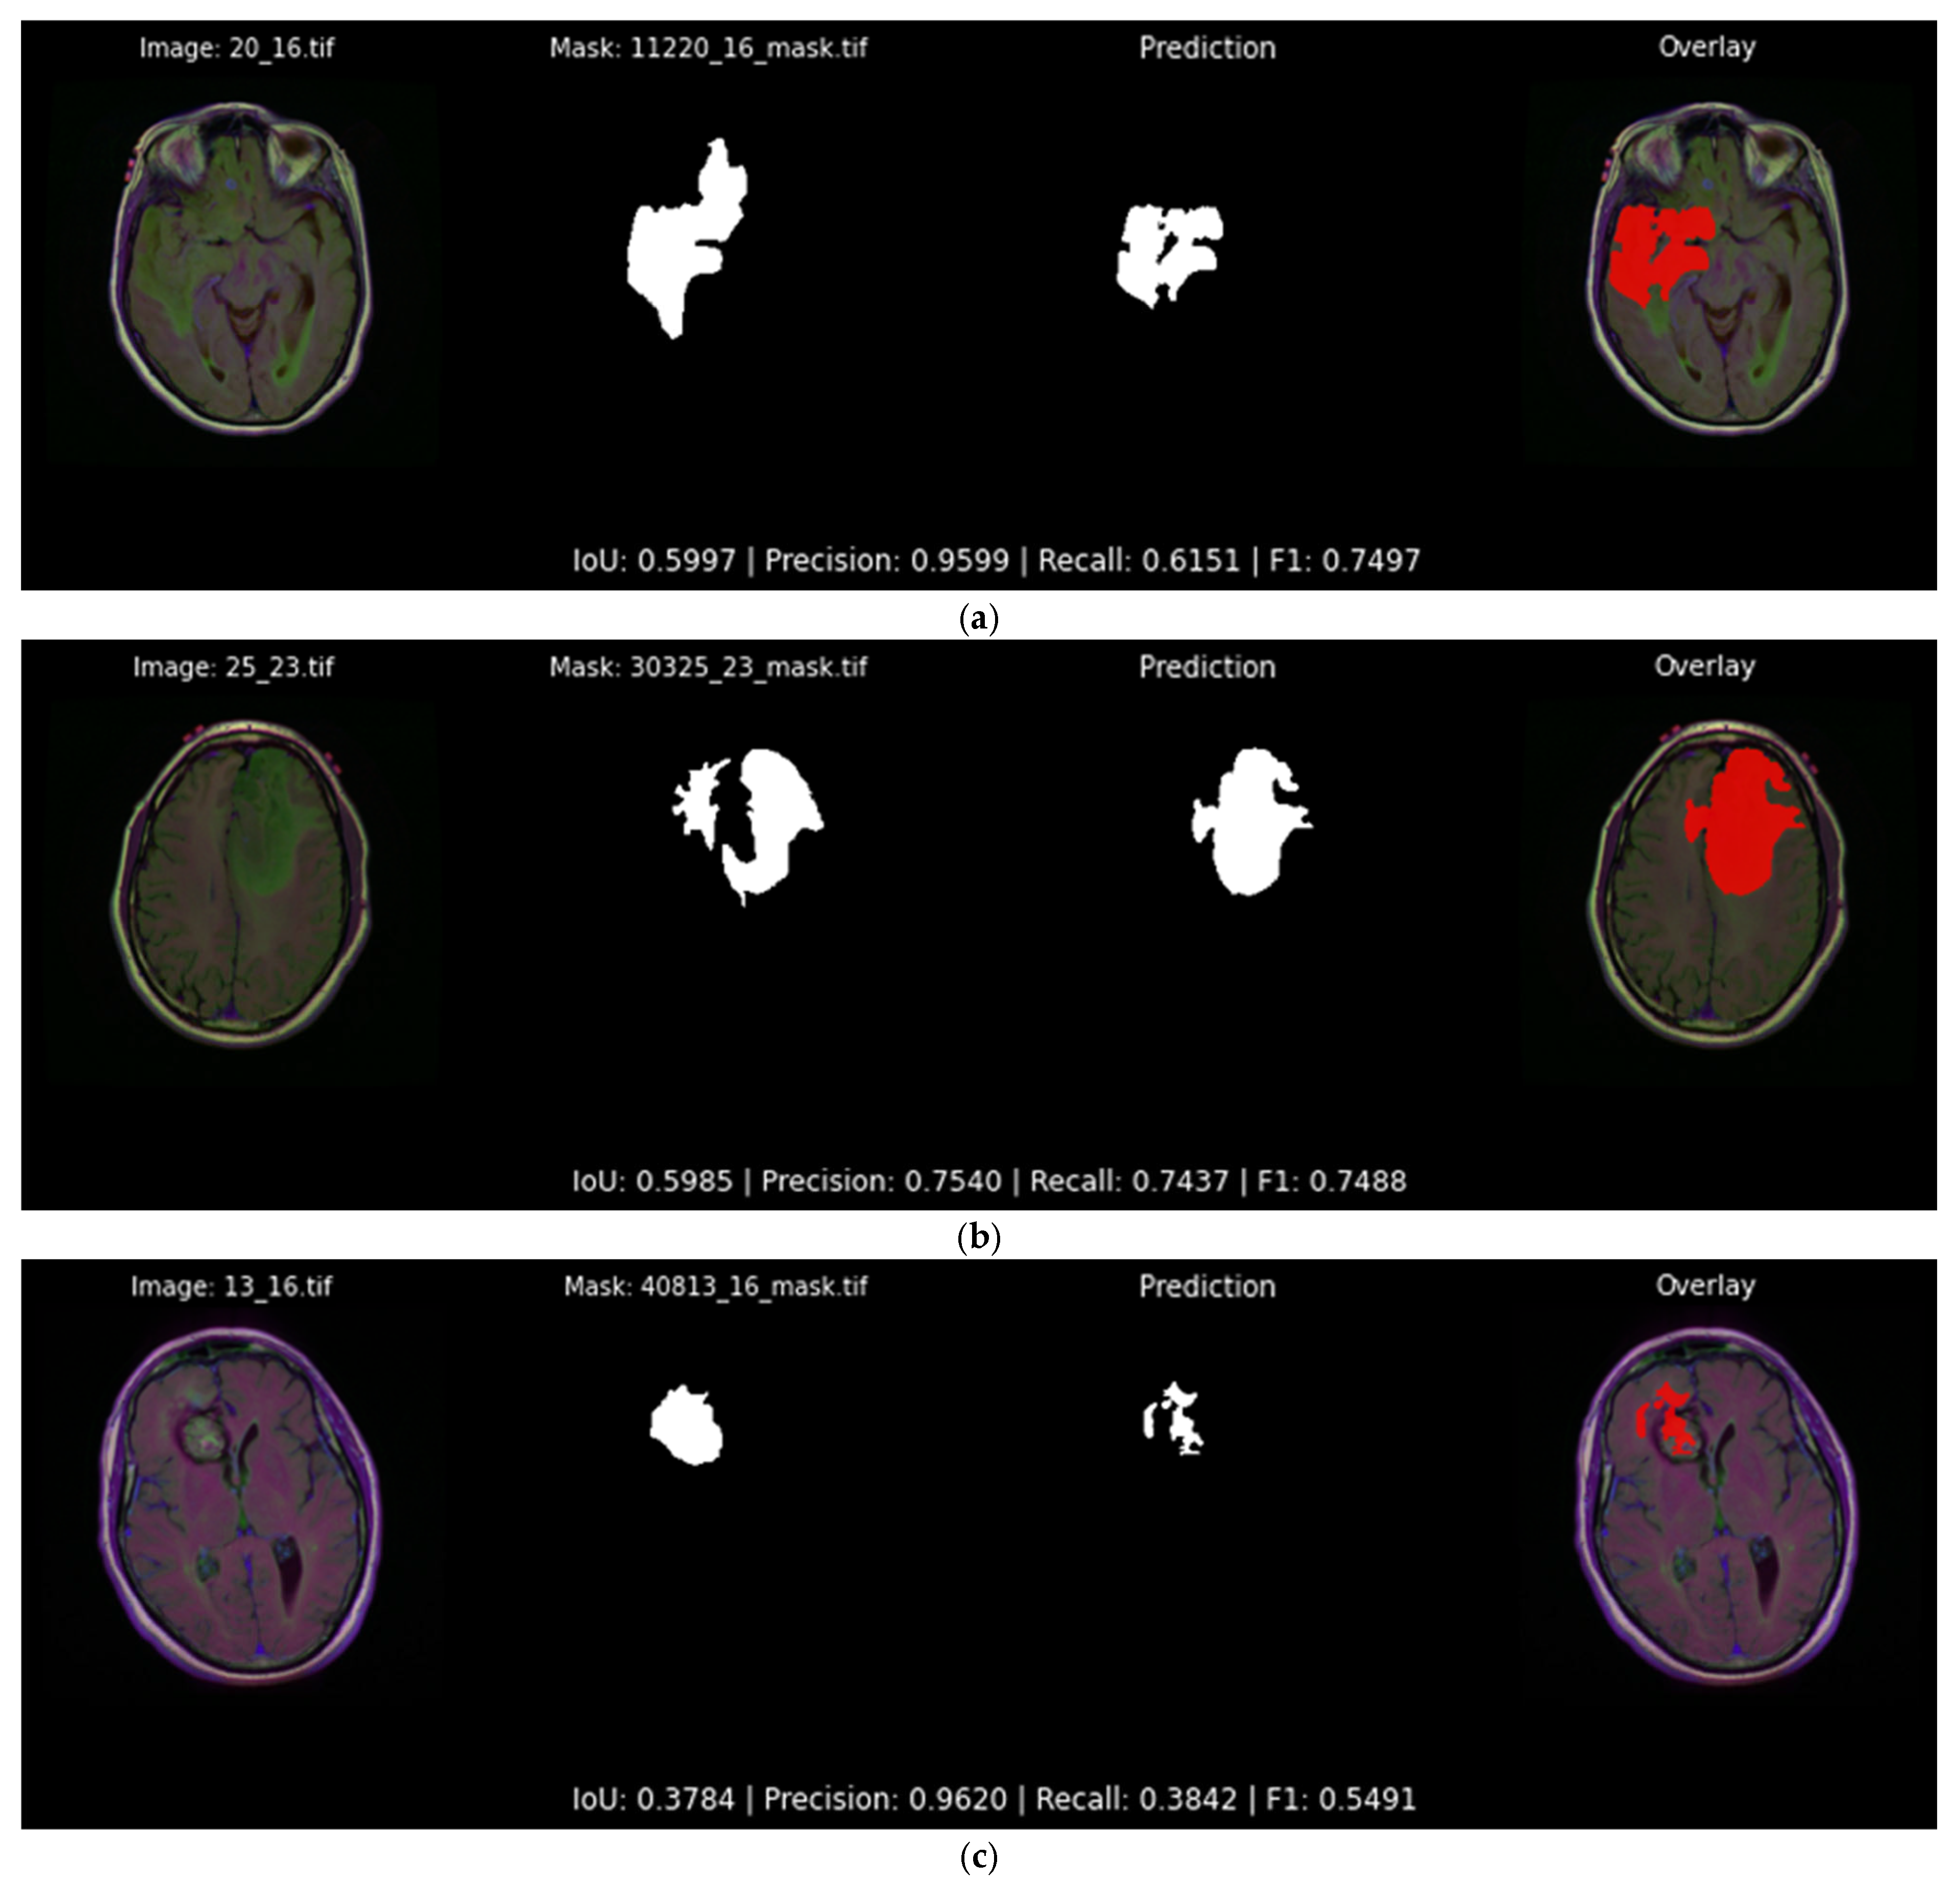

Conversely, Figure 14 showcases three examples in which the same model struggles, where irregular tumor shapes lead to fragmented or under-segmented predictions. The first and second slices still achieve moderate IoU values just below 0.60, yet noticeable portions of the tumor are missing. The third slice showcases the most challenging amongst the examples of Figure 14, where the network detects only a small fragment of the ground truth region, yielding an IoU of 0.378. Such cases highlight the inherent difficulty of the precise tumor segmentation and motivate the post-processing refinements described later in Section 4.3.

Figure 14.

Qualitative evaluation with examples in which the Attention U-Net and DiceBCE with softmax head predicts suboptimal and irregular tumor segmentation masks (IoU < 0.60). Each subfigure displays the original image, the ground truth segmentation mask, the predicted segmentation mask, and the original image overlaid with the predicted segmentation output mask (red) generated by the top-performing segmentation model: (a) showcases an example of a segmentation output of 0.599 IoU; (b) showcases an example of a segmentation output of 0.598 IoU; (c) showcases an example of a segmentation output of 0.378 IoU.